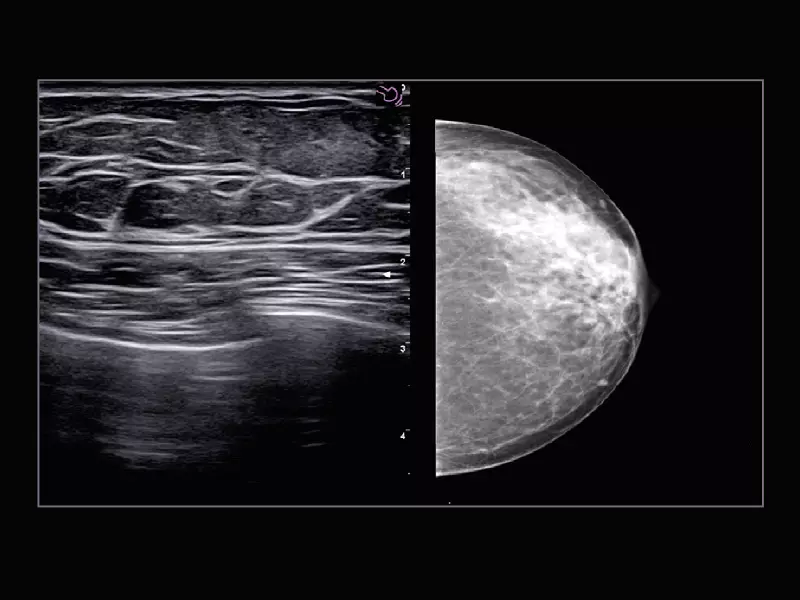

MyLab™9 Platform - Breast BodyMap and real-time ElaXto in Mammo

MyLab™9 Platform - Breast BodyMap and real-time ElaXto in Mammo

MyLab™X9 - Breast 01

MyLab™X9 - Breast 01

MyLab™X9 - Breast 02

MyLab™X9 - Breast 02

MyLab™X9 - Breast 03

MyLab™X9 - Breast 03

MyLab™X9 - Breast 04

MyLab™X9 - Breast 04

MyLab™X9 - Breast 05

MyLab™X9 - Breast 05

MyLab™X9 - Breast 06

MyLab™X9 - Breast 06